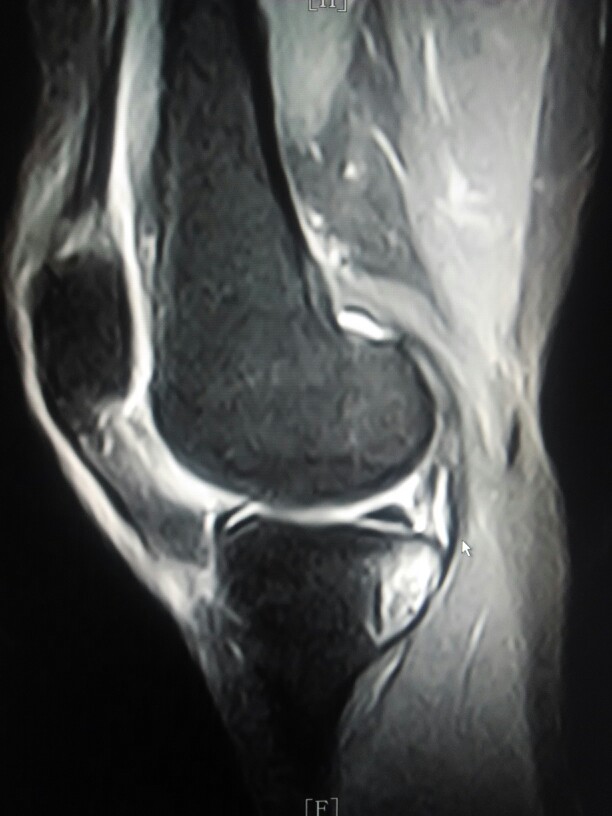

女性患者,50岁,右侧膝关节,出现肿痛,关节受限2年,加重2月。既往没有其他病史没有做过,膝关节的x光片,ct检查,近日来我院就诊,查膝关节的核磁共振扫描显示。右侧胫骨内侧平台下方可见片状稍长t2信号。外侧半月板后角可见小片状稍长t2信号影。关节腔内可见积液信号。大家讨论一下该病人胫骨平台是骨髓水肿还是其它病变。

接上个病例,女性,50岁,右侧膝关节肿胀活动受限2年